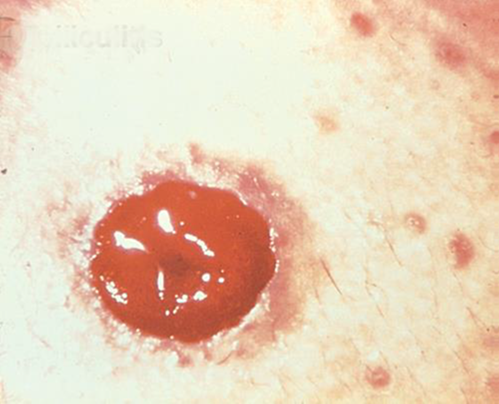

Pyoderma Gangrenosum

Popis/příčiny:

Zánětlivé kožní onemocnění, které se často vyskytuje u pacientů se zánětlivým onemocněním střev (IBD), jako je Crohnova choroba nebo ulcerózní kolitida.

Symptomy:

- Nepravidelně tvarované, červené, bolestivé, infikované vředy, s červenými až fialovými svinutými okraji; se objevují na nohou, hýždích, obličeji a peristomální oblasti.